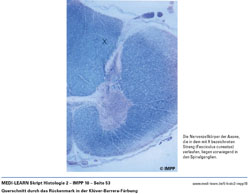

• Querschnitt durch das Rückenmark in der Klüver-Barrera-Färbung